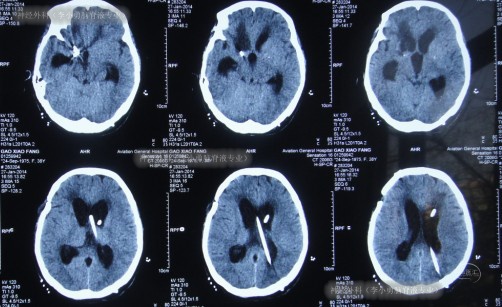

2014年1月2日即转入第3家医院后第1天(分流术后第31天)查头颅CT(图-10)示脑室扩张和脑室周围水有所加重。

图-10:分流术后31天头颅CT

次日即2013年1月17日,查头颅CT(图-11)示脑室有所再度扩张,腰穿测压140,脑脊液白细胞1100,医生考虑此种情况与相关药物减量有关,遂即恢复“高剂量”的使用,并加口服相关药物治疗。

图-11:分流术后46天头颅CT

入院当天进行头颅CT示脑积水分流术后脑室显著扩张,脑室周围水肿(图-13)。

图-13:2014年1月20日头颅CT

术后当天患者症状就改善为:可简单言语,但因发声细小仍难辨别;经口能进少量流食;查头颅CT示脑室较前缩小,原脑室分流管去除,侧脑室外引流管位置良好(图-14)。

图-14:2014年1月20日术后头颅CT